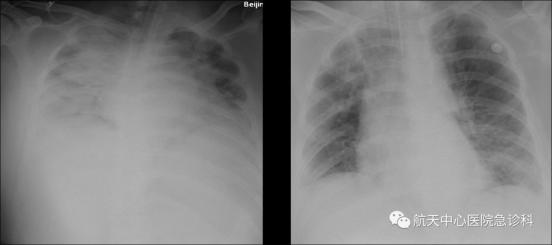

下呼吸道感染是指聲門以下的感染,可能涉及氣管、支氣管和肺部,癥狀包括氣管炎、支氣管肺炎等。什么是下呼吸道感染?下呼吸道感染是指發生在聲門以下的感染,包括急性支氣管炎和肺炎。而且下呼吸道感染越早(1歲前發生)、越頻繁(三次及以上)或越重(需要住院治療)時,成年后因呼吸道疾病過早死亡的風險增加越多(增加1.1~3.3倍)。